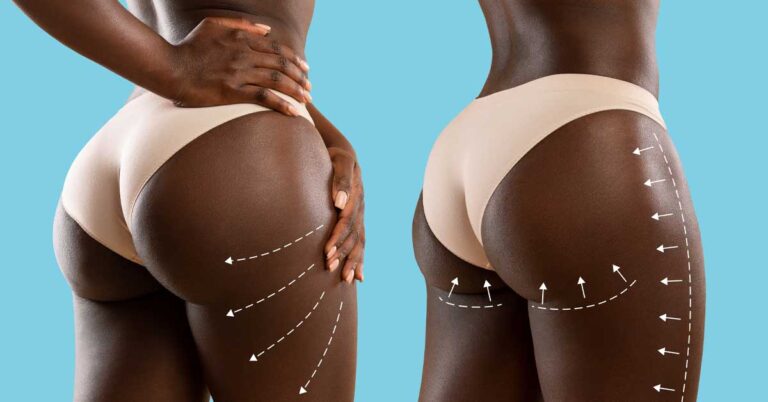

How Your Belly Button Changes After a BBL? Are you considering a Brazilian Butt Lift (BBL) but concerned about how it might affect your belly

BBL After 10 Years: The Truth About BBL Longevity The Brazilian Butt Lift (BBL) has become increasingly popular as a transformative cosmetic procedure, offering individuals

Fat Embolism Syndrome After BBL: Symptoms, Diagnosis, and Treatment Are you considering a Brazilian butt lift (BBL) to enhance your curves? While the procedure is